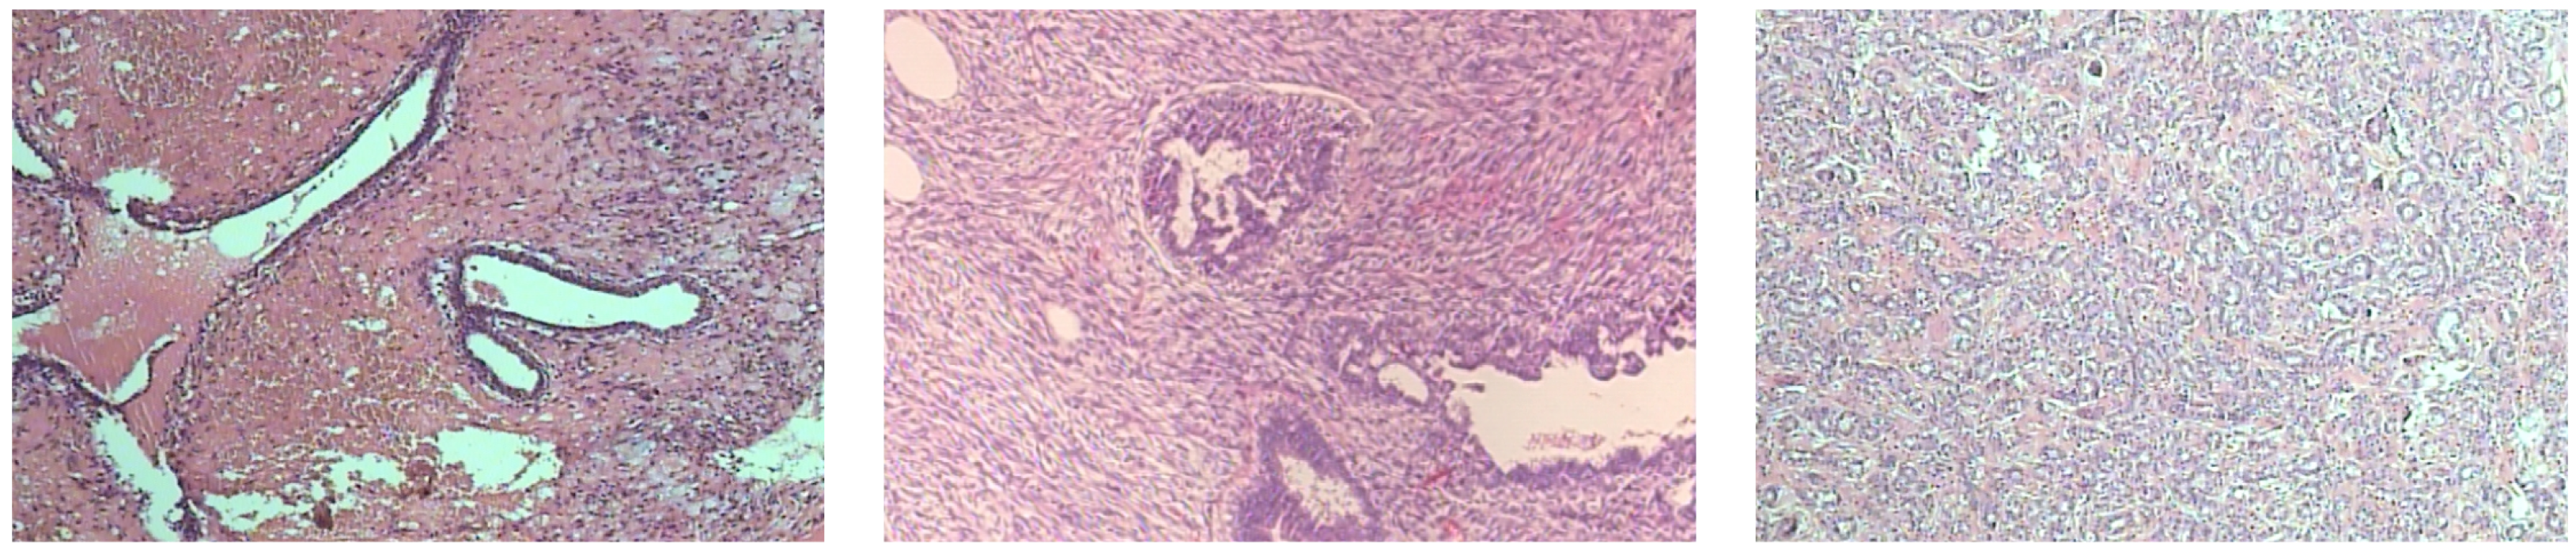

Figure 1 and Figure 2 present three representative samples of benign and malignant breast histopathology from the dataset, respectively, at 200× magnification.

Figure 1. Representative benign breast histopathology images from the BreakHis dataset at 200× magnification. From left to right: adenosis, fibroadenoma, and tubular adenoma.